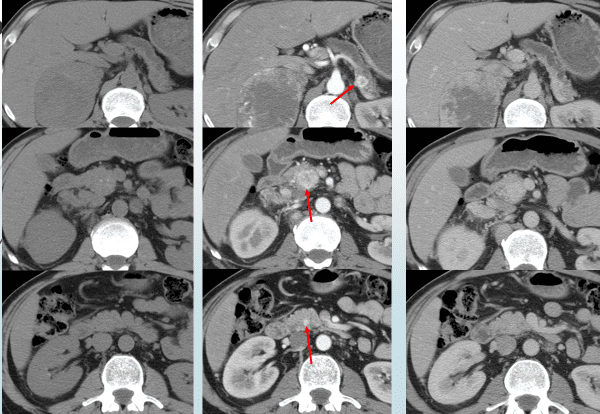

Рисунок 1. Множественные нейроэндокринные опухоли поджелудочной железы. Определяются только на фоне внутривенного введения контрастного препарата.

Рисунок 2. Нейроэндокринная опухоль желудка. Определяется только на фоне внутривенного введения контрастного препарата.

Рисунок 3. Нейроэндокринная опухоль кишечника. Определяется только на фоне внутривенного введения контрастного препарата.